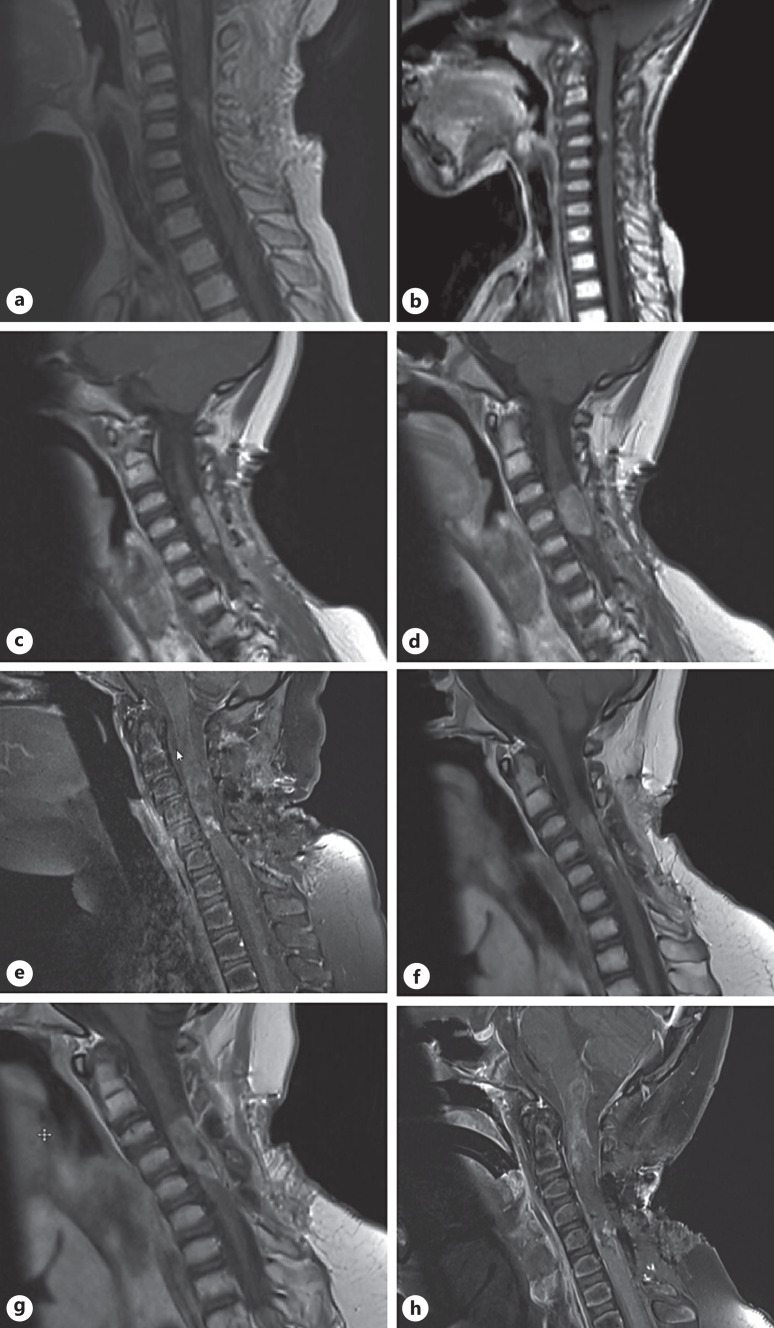

Case presentation: An 8-year-old girl was transferred from her home country to Switzerland for treatment of a recurrent intramedullary tumor of the cervical spine extending from C2-C7. The tumor was primarily diagnosed as an ependymoma of the spinal cord. Prior to her transfer to our department, the patient had undergone subtotal resection of the lesion, radiation therapy, multiple chemotherapy regimens, and biopsy of the recurrent tumor. Clinically, the patient presented with tetraparesis and had recently experienced worsening upper extremity weakness with complete loss of hand function. We performed a near total resection of the recurrent tumor. Ultra-fast Nanopore seq® based DNA methylome profiling allowed confirmation of the molecular diagnosis of a high-grade neuroepithelial tumor (HGNET-MN1) consistent with astroblastoma in less than 2 h, with subsequent molecular workup revealing a EWSR1-BEND2 fusion. After surgery, the patient gradually regained function in her hands. She was sent to a specialized pediatric rehabilitation center, and while the tumor was being followed radiologically with no adjuvant treatment planned, the patient presented with a relapse of the tumor in only 3 months. Given the acute worsening of radiating pain and sudden respiratory failure, a cervical decompression was performed. MRI of the cervical spine showed infiltration of the lower aspects of the brainstem. The patient was offered palliative comfort care.